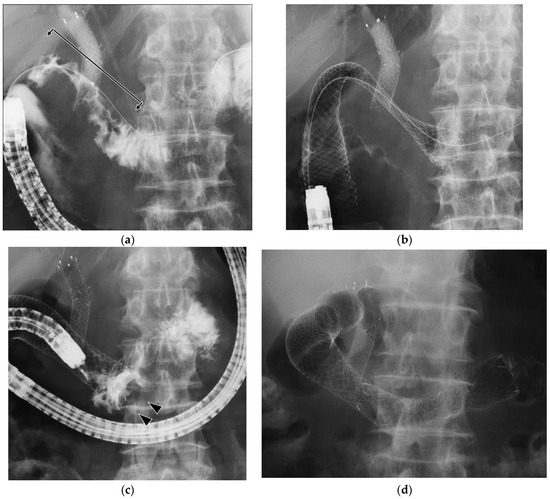

3.2. Procedure of Duodenal Stenting